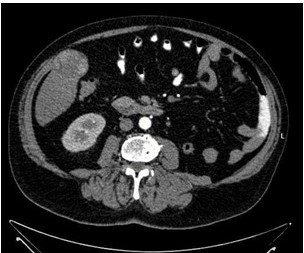

Reportamos el caso de un paciente masculino de 65 años de edad quien consultó por control. Con antecedente de carcinoma de células claras de riñón izquierdo estadio II ameritó nefrectomía radical izquierda y adenocarcinoma de próstata Gleason 9 avanzado oligometastásico, recibió tratamiento con bicalutimada, zoladex y abiraterona acompañado de radioterapia 39 ciclos; hábito OH acentuado, durante la consulta se le evidencia mediante ecografía abdominal lesión ocupante de espacio de segmento V hepático. Fue estudiado con tomografía con protocolo hepático donde se evidencia imagen redondeada de 4,7 cm, que presenta captación discreta heterogénea periférica en fase arterial, lo que sugiere área de necrosis central y un wash out lento en fase de eliminación, dicha lesión está ubicada en el segmento V y se encuentra en íntima relación con los músculos de la pared abdominal anterior ( Figura 1 y 2), Fibroscan en el cual no se evidencia cirrosis hepática, sin embargo, en vista del tamaño del tumor y antecedentes del paciente se decide realizar resonancia magnética nuclear (RMN), en la cual se evidencia lesión redondeada, bien delimitada, heterogénea que mide 5 cm x 4,5 cm x 4,2 cm en lóbulo hepático derecho segmento V con un volumen aproximado de 50 cm3 (Figura 3 y 4), pruebas de funcionalismo hepático alteradas AST 301U/l, ALT 206U/l, alfafetoproteína 244,10 ng/mL, antígeno carcinoembrionario 2,23 ng/mL, Ca 19-9 1,00 U/mL, con CT PET del año anterior negativo, por lo cual se decide realización de intervención quirúrgica con sospecha diagnóstica de carcinoma hepatocelular.